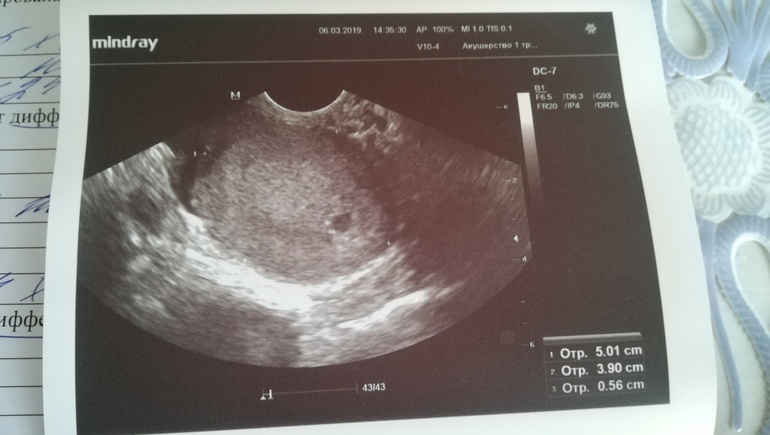

У меня ровно в 5 недель ПЯ - 5 мм. В 5,6 дней - 16 мм, ЖМ - 4 мм, эмбрион проглядывается, то ещё не чётко. Срок очень маленький. Рано вы паникуете. Эмбрион на 7 неделе нужно смотреть.

Ну рост хгч хороший. Это сколько недель. У меня в первую Б эмбрион и сб+ было в 6+3, во вторую 6+4)))

На 21дпо было пя 9мм, эмбрион и сб увидели ровно через неделю. Про размеры у всех по-разному. У меня эмбриончик для моего срока маленький, но сказали это ни о чем не говорит, со временем догонит. Не переживайте раньше времени ))